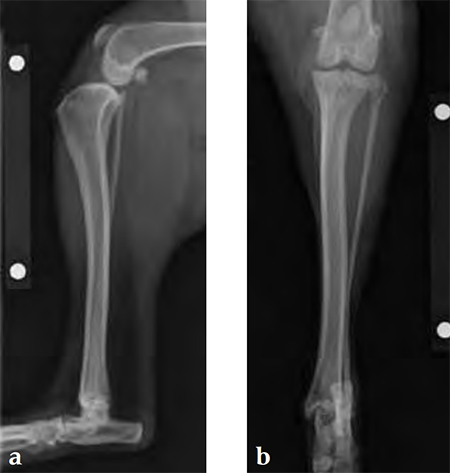

Case 2: Australian cattle dog

(Case provided by Brian Beale, Houston, USA)

An 8-year-old, female, spayed, 24 kg Australian cattle dog. This breed has short stocky legs and is very energetic and strong. The added strength of the 3.5 mm plate over the TPLO 2.7 mm plate was an advantage. The smaller head profile and shorter length of the TPLO 3.5 mm small stature plate allowed it to fit nicely on this patient.